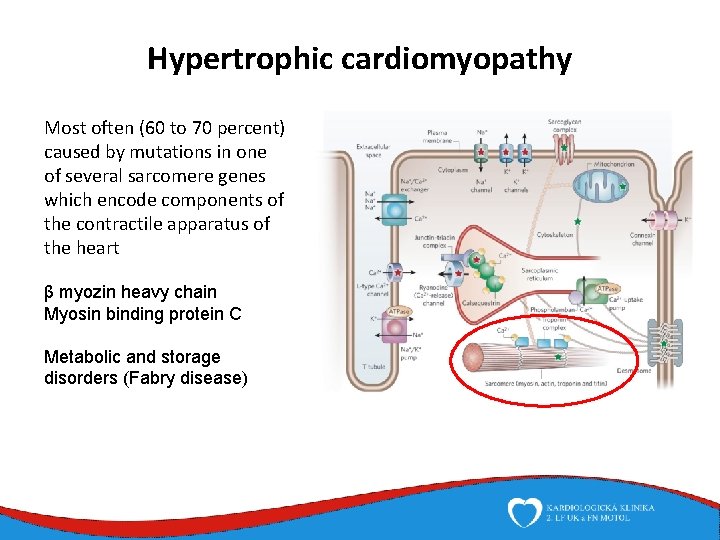

Hypertrophic cardiomyopathy Most often (60 to 70 percent) caused by mutations in one of several sarcomere genes which encode components of the contractile apparatus of the heart β myozin heavy chain Myosin binding protein C Metabolic and storage disorders (Fabry disease)